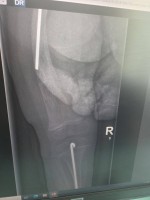

Madzia choruje na wrodzoną łamliwość kości typu III (osteogenesis imperfecta) – rzadką, genetyczną chorobę tkanki łącznej, która powoduje skrajną kruchość kości. Złamań doznała już w życiu płodowym, a jej organizm nie produkuje kolagenu. Choroba jest nieuleczalna, a leczenie ma charakter objawowy i obejmuje stałą rehabilitację, liczne operacje, stabilizację kości oraz specjalistyczną farmakoterapię. Dziewczynka ma za sobą już kilka poważnych zabiegów oraz kilkanaście podań leków wzmacniających kości. Przed nią kolejne operacje i intensywna fizjoterapia, bez której trudno byłoby myśleć o większej samodzielności.

Foto: Licytacje dla Madzi Sulki.